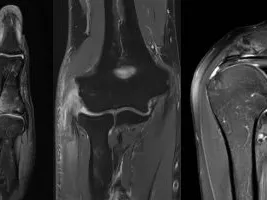

The purpose of this online fellowship is to discuss different UPPER EXTREMITY MSK topics and start practicing immediately by reading selected cases together with the mentor. The upper extremity module discusses the shoulder rotator cuff and instability, elbow, wrist, and hand, together with some tumor cases. The selected cases for reading are from our teaching file and allow the participant to practice with common cases that may appear in your daily worklist.

- Lectures on common pathology of the upper extremity:

- Shoulder rotator cuff

- Massive tears

- Rotator cuff mimickers

- Shoulder instability

- Elbow